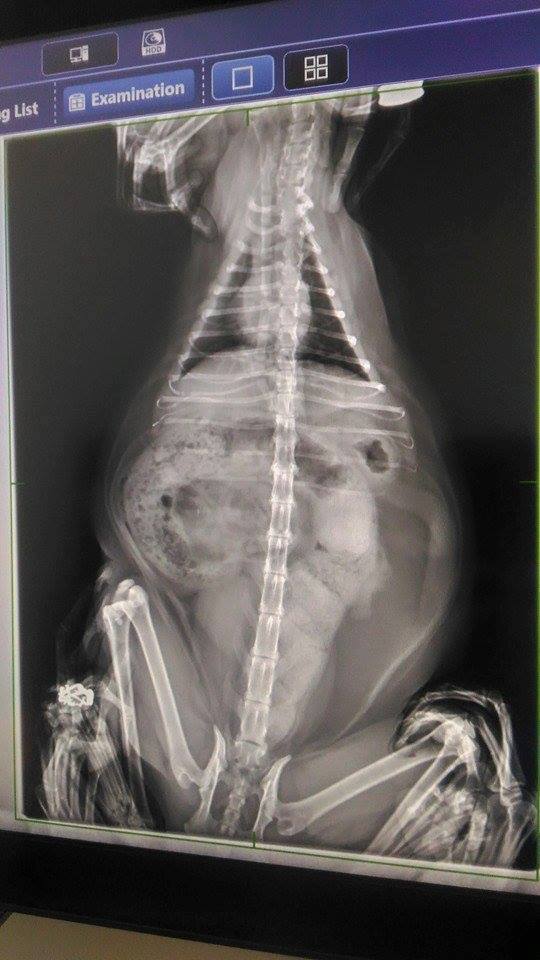

主題: 因巨結腸症無法順利排泄的小黃 申請者姓名: 臺北市支持流浪貓絕育計劃協會 花色: 申請日期: 2017-02-10 11:55:20 申請者部落格: 申請者臉書網址: 所在縣市/合作醫院: 台北市/澄諾動物醫院 治療費用: 5500元 需求人數: 13人 已結案 (2022-05-13 15:15:22) 報名人員: youngshiang(已付款)、彭小花(已付款)、Peiying Liu(已付款)、Liz x2(已付款)、Yi Ru Chen(已付款)、IRIS(已付款)、Kyra Chu(已付款)、樹下的紅果實(已付款)、陳盈年(已付款)、Missy(已付款)、kclin(已付款)、woolet(已付款)、 候補人員: 動物病情說明: 小黃原先是協會粉絲團接獲通報人通報一隻腿上長了大腫瘤的浪喵喵,

但小黃因患有巨結腸症,導致排便尚無法像一般貓咪一樣順利,

本次回診則由於小黃幾日無便

照護員見他時常蹲廁所,用盡力氣到幾乎癱軟

卻仍無法順利排便

緊急於過年期間安排就醫治療並帶回

小黃1/29回診挖大便 1/29,